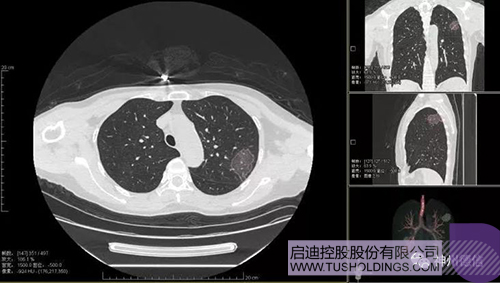

神州德信新冠肺炎檢測及智能量化分析系統

啟迪戰(zhàn)略投資企業(yè)神州德信作為國內領先的肺部影像人工智能企業(yè),針對新型冠狀病毒肺炎開發(fā)了智能檢測及量化分析系統,并在陜西、重慶等地定點醫(yī)院投入使用。該系統在疑似病例大規(guī)??焖俸Y查及精準診斷方面發(fā)揮了重要作用,特別是其具有的肺炎患者臨床影像跟蹤量化隨訪功能,為快速有效阻斷疫情擴散提供了有力武器。